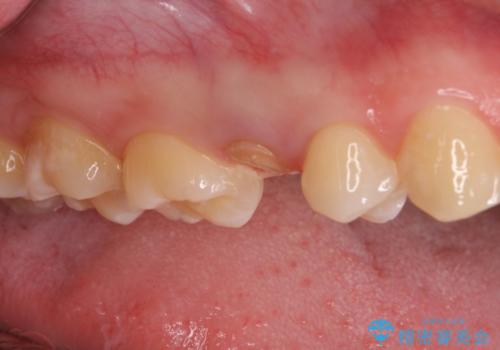

他院で虫歯治療を複数行っており、原因となりうる歯がいくつかありました。まずレントゲン上最もあやしい右上から治療開始しました。

右上の被せものを除去したところ、中で歯が割れていたため、部分矯正で引っ張り出すことになりました。